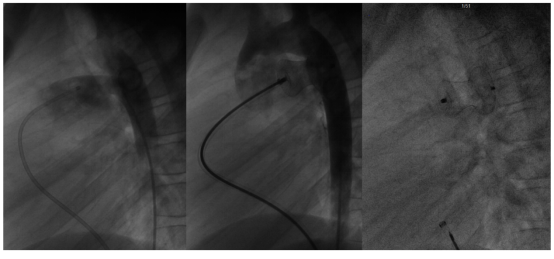

入院后,我院心内科团队第一时间为次仁拉措开展全面细致的检查评估,结果显示其动脉导管未闭内径达12mm,已合并严重肺动脉高压及慢性心功能衰竭,病情十分危急。团队迅速制定个性化诊疗方案,先给予强心、降肺压等对症支持治疗,密切监测患儿病情变化。待其心功能逐步改善、达到手术标准后,于2026年3月31日为其成功实施动脉导管未闭介入封堵术。

整个手术过程十分顺利,微创介入的方式最大程度降低了手术创伤。术后第二天,次仁拉措便能自主下床活动,她稚嫩的脸上露出笑容,开心地说:“我感觉非常好,身体有劲了!” 看到孩子病情好转,家属及陪同的当地政府工作人员激动不已,向心内科医护团队献上象征敬意与感谢的彩色哈达,真挚的情感让现场暖意融融。